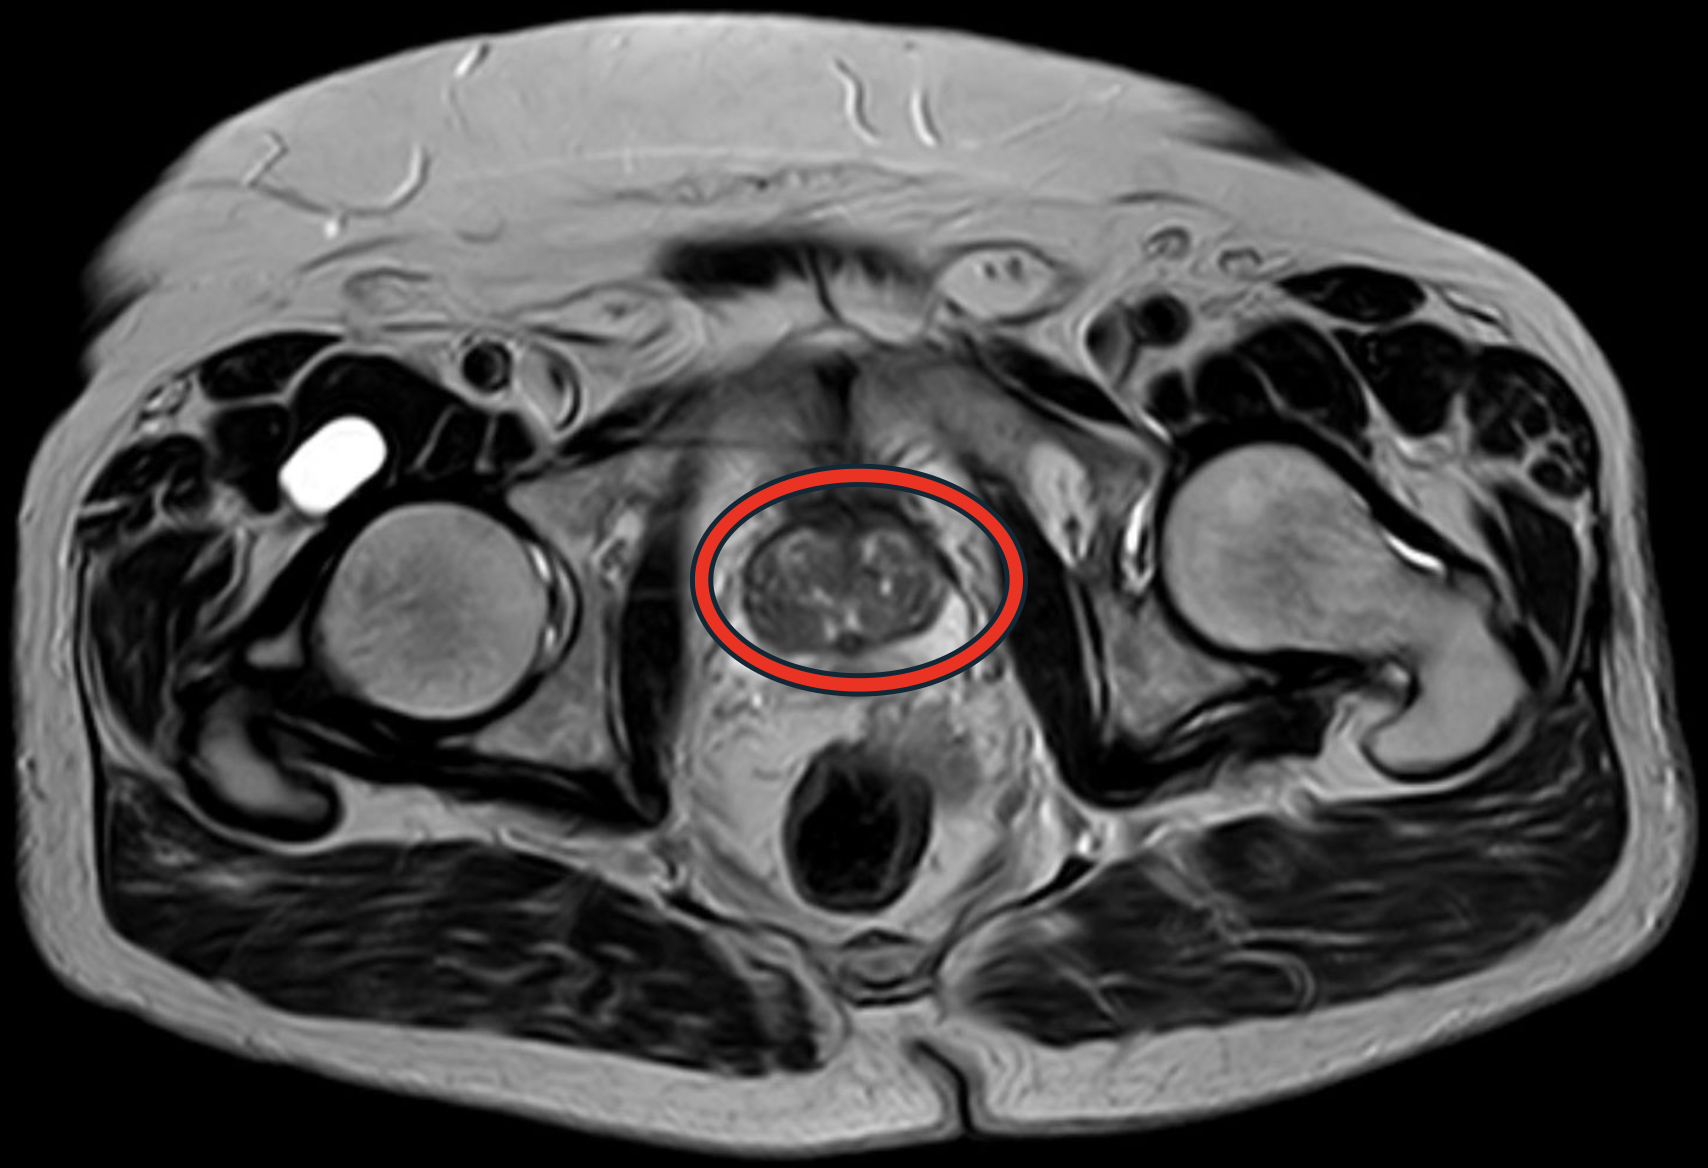

2.67 Das Bild zeigt eine axiale Magnetresonanztomografie des Beckens.

Welche anatomische Struktur ist innerhalb der roten Markierung dargestellt?

- (A) Rektum

- (B) Prostata

- (C) nicht gefüllte Harnblase

- (D) Skrotum

- (E) Uterus